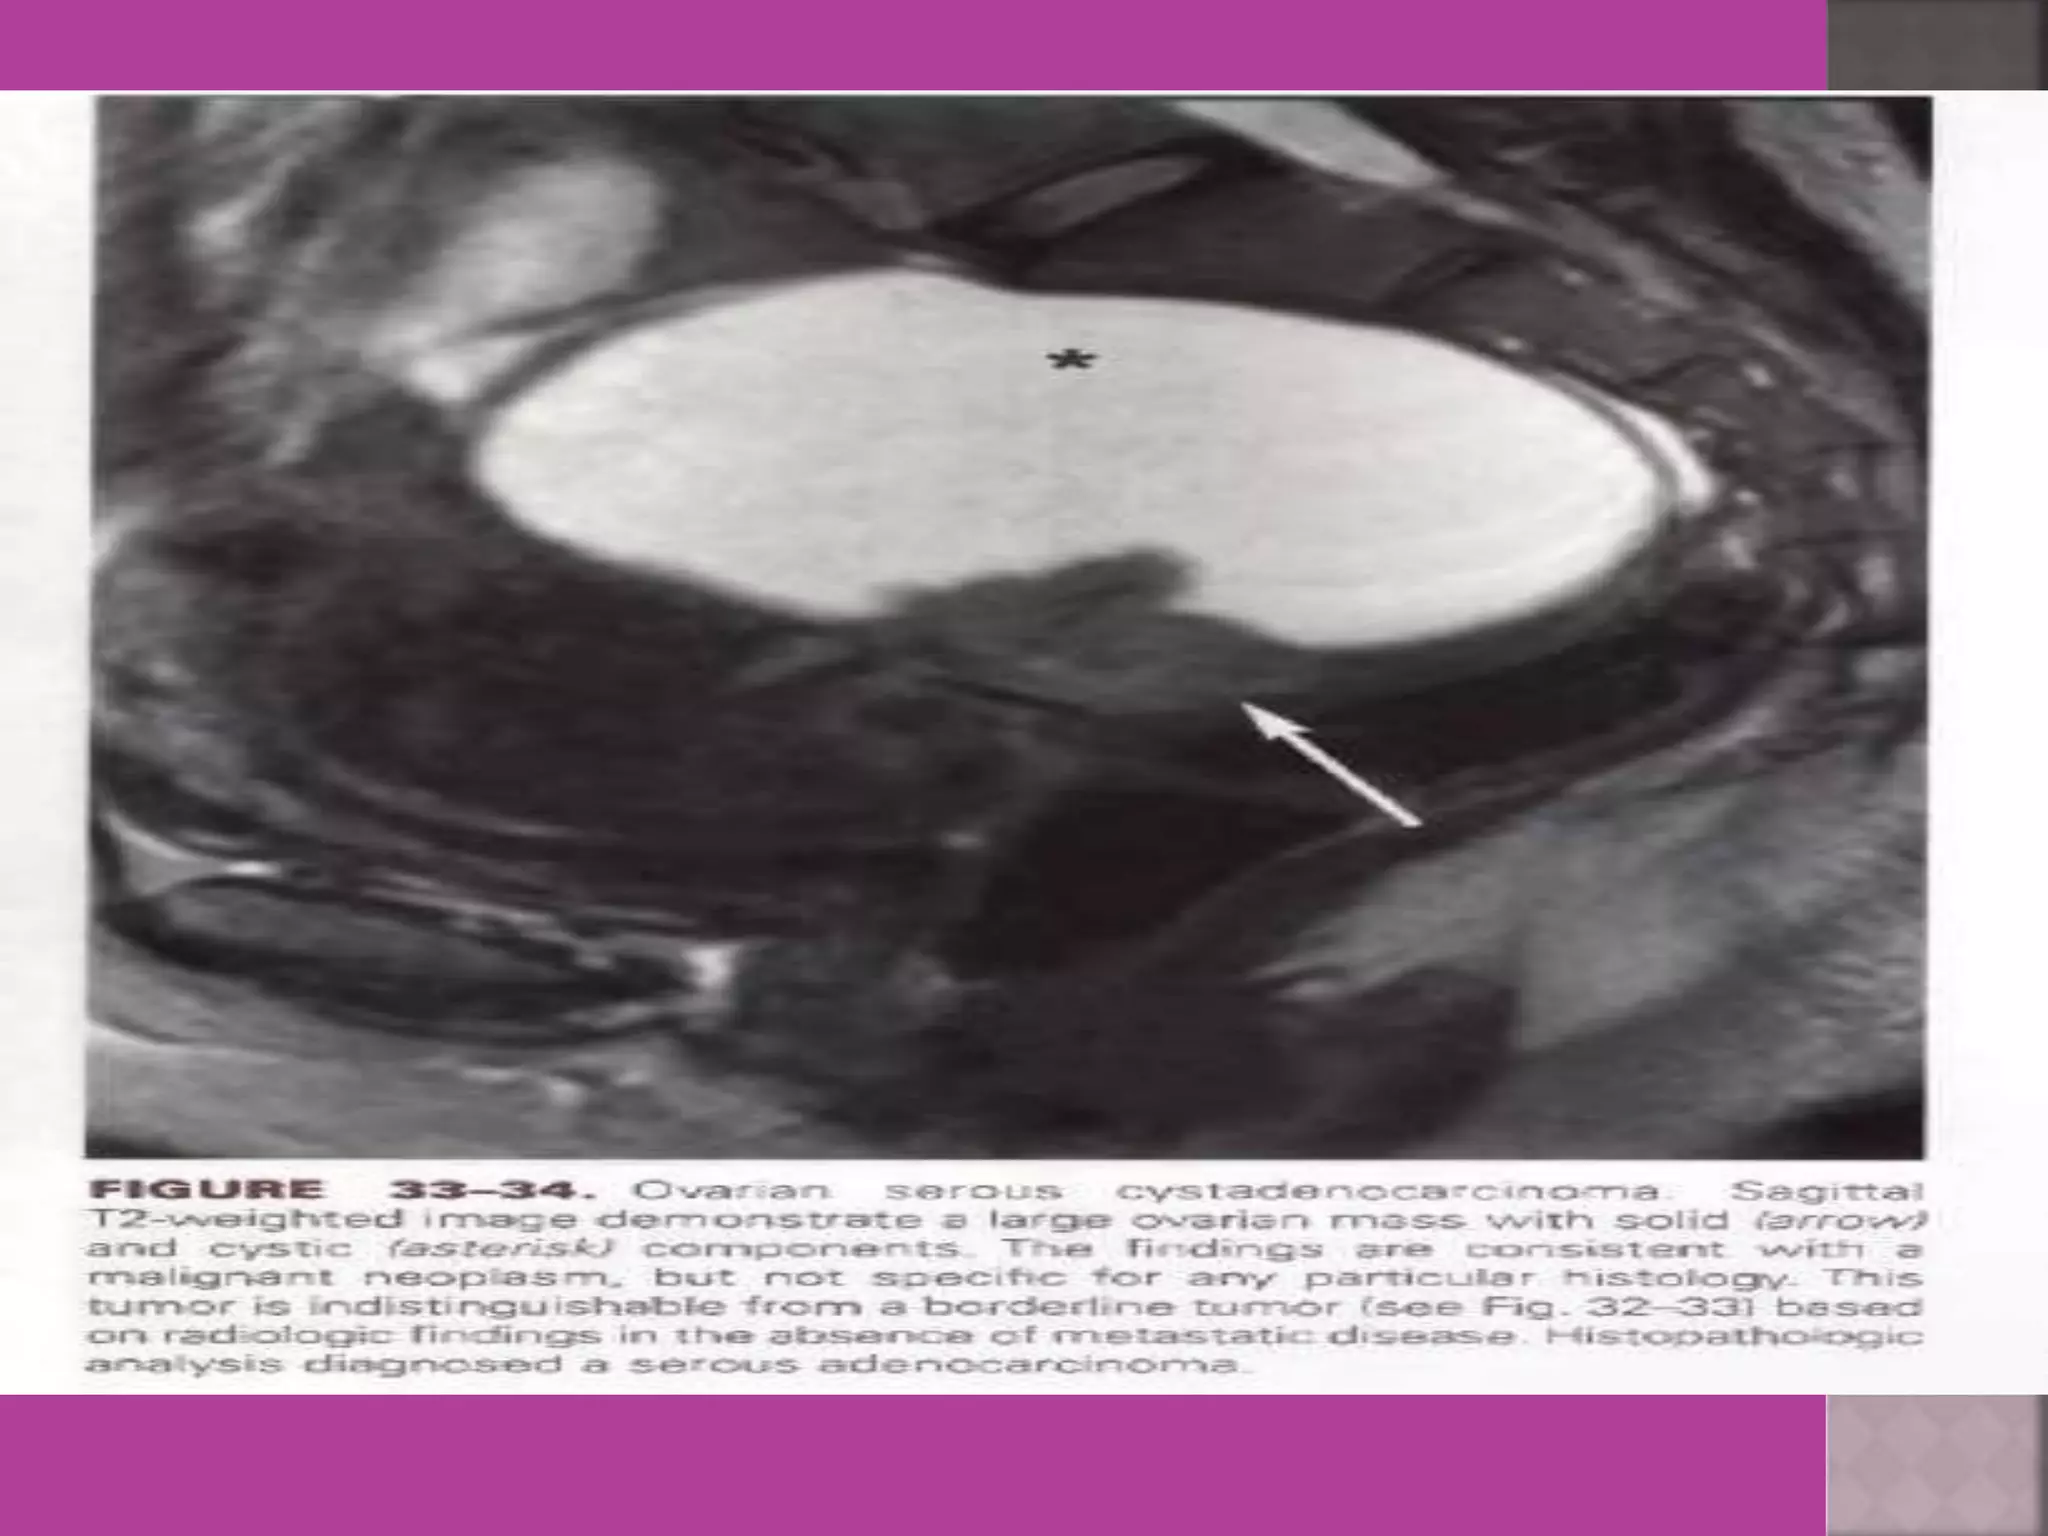

3. ovarian cancer—malignant versus

benign mass, ascites , retroperitoneal node >

1cm , Bowel bladder , ano rectal . Parietal

peritoneum , liver and or omental

metastasis.

Ovarian Tumor